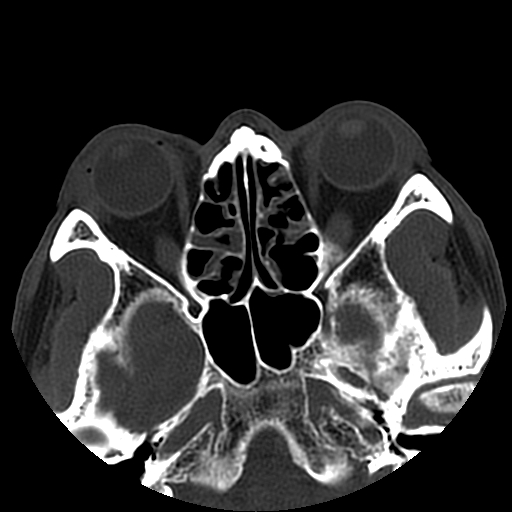

以下是引用liaoqiang在2008-7-16 21:15:00的发言:[br]右侧鼻骨骨折

以下是引用zxd95在2008-7-16 21:39:00的发言:[br]右侧上颌骨额突骨折。[br][br][br][br]